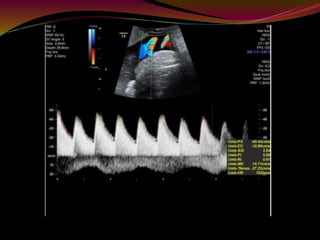

MCA

 The middle cerebral artery is the vessel of choice to

 easy to identify,

 is highly reproducible

 provides information on the brain-sparing effect.

 In addition, the MCA can be studied easily with an

angle of 0 degrees between the ultrasound beam and

the direction of blood flow providing information on

the true velocity

 The MCA should be sampled soon after its origin from

the ICA

 IUGR is associated with increased blood flow to the fetal

Brain.

 This increase in blood flow during diastole can be

demonstrated by Doppler ultrasound of the MCA.

 This effect is termed the brain-sparing effect and is

demonstrated by a lower value of the MCA PI